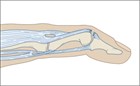

変形を伴う指先の損傷を訴えて患者は来院する.指先にボールが当たったり,静止した物体にぶつかったりしたとき等に,遠位指節間(DIP)関節が屈曲位となり,遠位指節骨の基部の背面に痛みと圧痛が生じる.この損傷は,比較的軽微な外傷(暗闇でライトのスイッチに手を伸ばしている間に指をぶつける等)で発症することもあれば,指の背面に直接打撃を受けた結果として発症することもある.DIP関節上の腫脹や皮下出血を伴う場合と伴わない場合がある.指を安静にしているか伸展位で保持しようとしても,損傷したDIP関節は軽度または中等度の屈曲位のままである(図106.1).